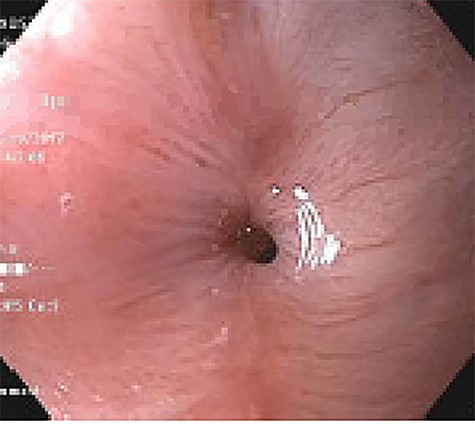

Approximately 2 months into his postoperative course, he returned with symptoms of dysphagia. esophagogastroduodenoscopy (EGD) revealed benign-appearing stenosis at the level of the esophagogastric anastomosis. This was initially dilated with a balloon. However, due to recurrent symptoms, a fully covered SEMS was placed to alleviate stricture (Figs 1, 2). The patient did well for nearly 2 months before returning with recurrent symptoms. A new web was visualized causing complete luminal obstruction (Fig. 3). This was unable to be traversed in antegrade fashion, requiring retrograde access via the jejunostomy utilizing guidewire. A pediatric colonoscope was able to be passed over the guidewire and dilate before subsequent SEMS deployment (Fig. 4). This stent was secured using 2-0 polypropylene suture via Overstitch device (Fig. 5). The initial SEMS was found to have migrated to the mid portion of the gastric conduit. However, due to the small caliber of the proximal stricture and to avoid disrupting newly deployed stent, the initial SEMS was left in place.